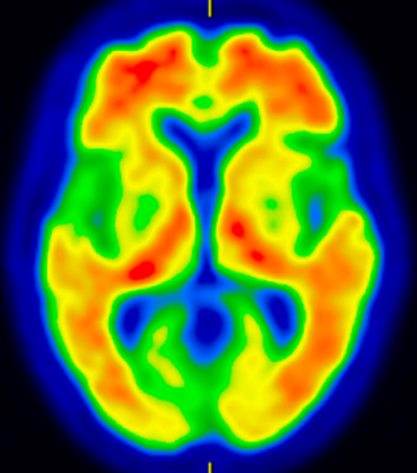

* 脳血流SPECT(図1):それぞれの認知症に特徴的な血流低下所見を確認して、鑑別診断の精度を高めます。

図1 アルツハイマー型認知症の脳血流SPECT